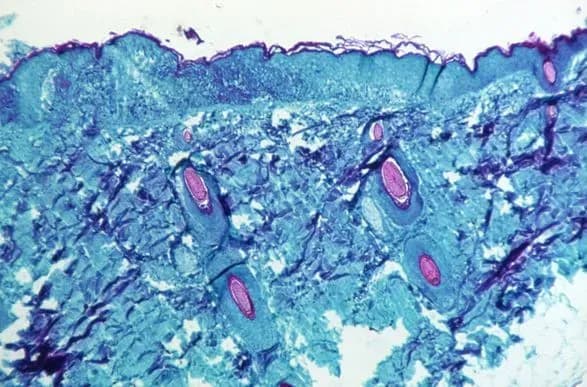

Большинство инфекций, обнаруженных во всем мире, до сих пор не были тяжелыми. Многие случаи инфицирования, но не все были зарегистрированы у мужчин, которые имели половые контакты с мужчинами. Симптомы включают лихорадку и характерную бугристую сыпь.

Болезнь, в основном встречающаяся в Западной и Центральной Африке, является вирусной инфекцией, впервые зарегистрированной в Демократической Республике Конго в 1970-х годах.